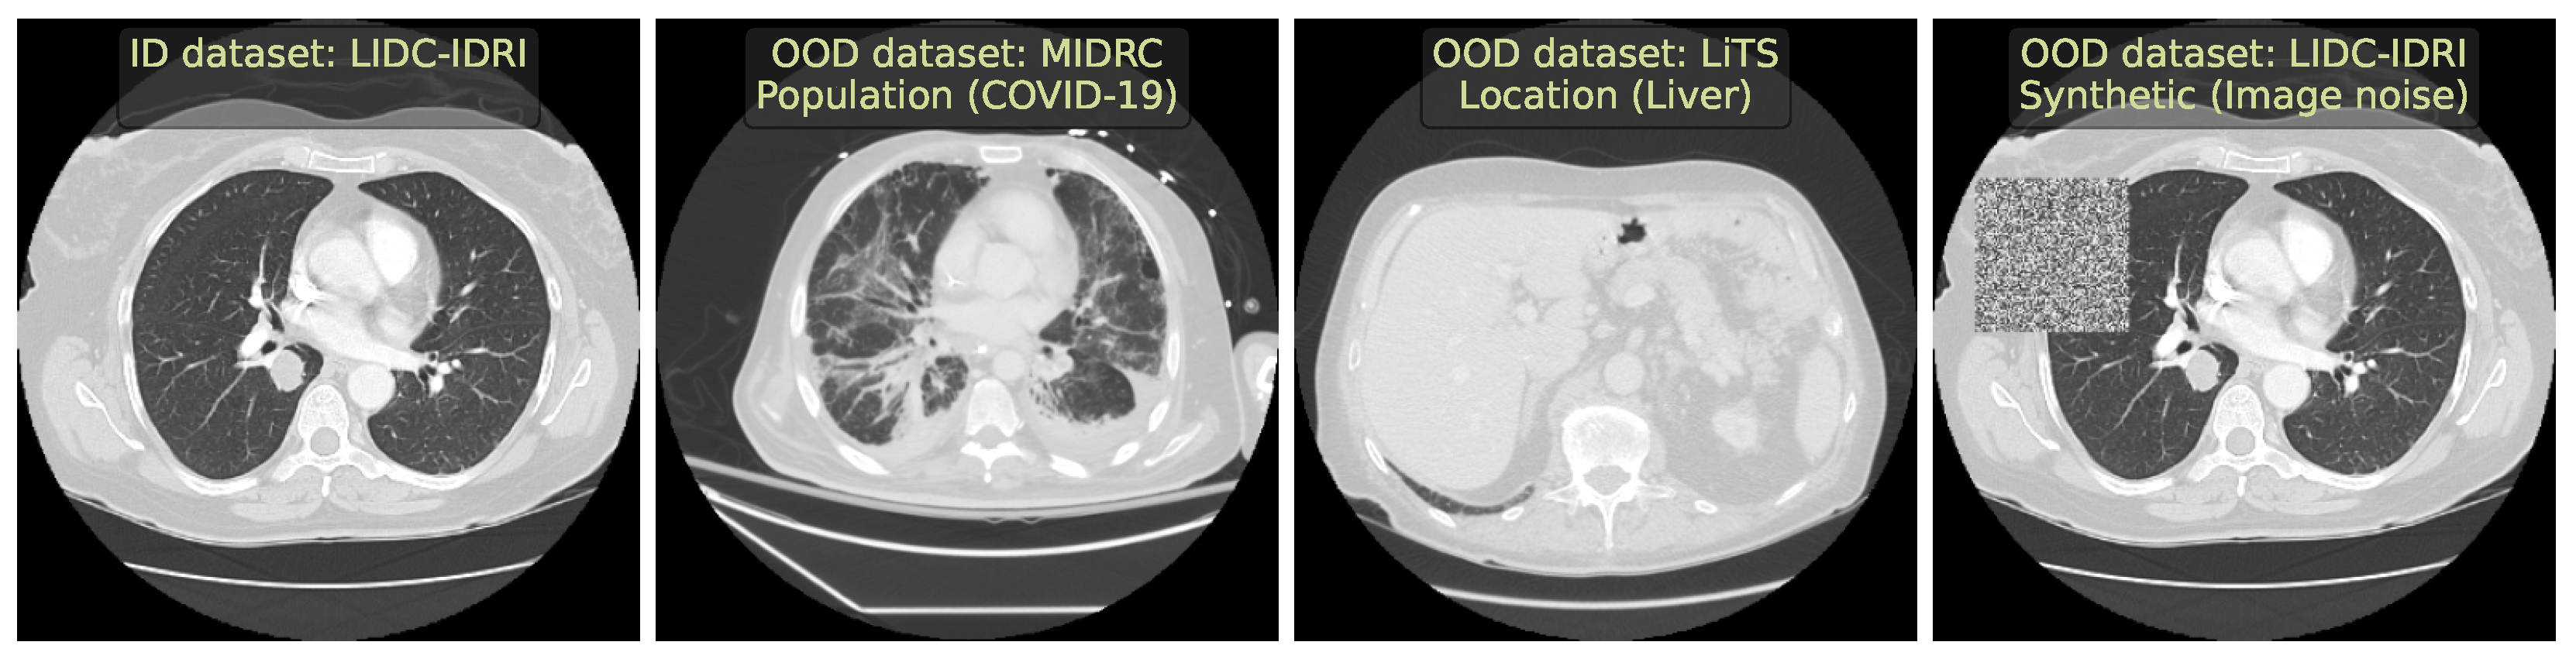

2. Data

- We included two large publicly available CT and MRI in-distribution (ID) datasets to cover the most frequent volumetric modalities.

- We selected diverse OOD datasets that simulated the clinically occurring sources of anomalies: changes in acquisition protocol, patient population, or anatomical region. All these datasets are publicly available.

2.1. Lung Nodules Segmentation